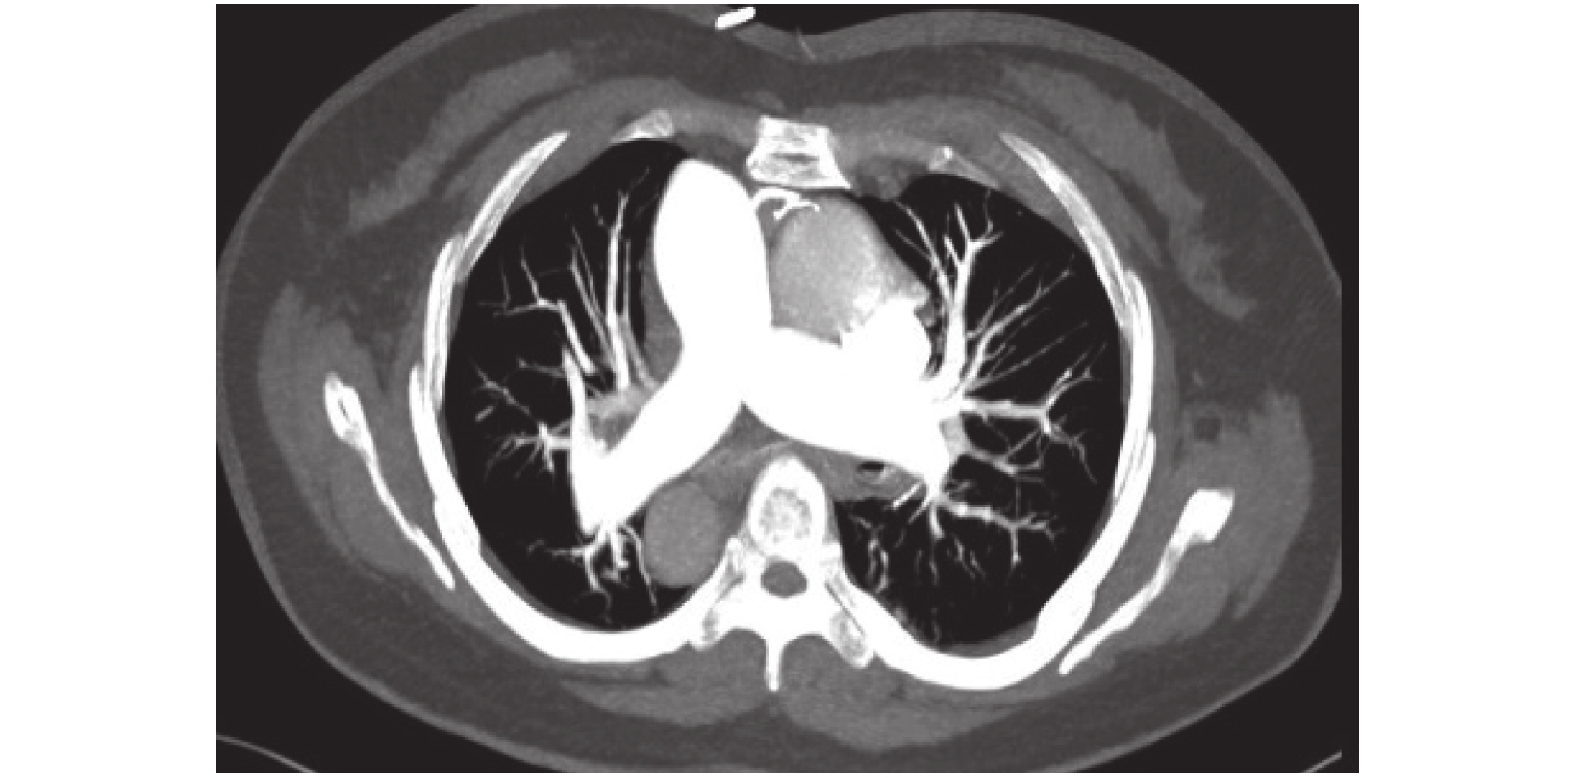

7 月 28 日患者無明顯誘因突然出現氧飽和度下降到 80%,心悸氣促較入院前明顯加重,予以面罩吸氧(氧濃度約 40%),氧飽和度可維持在 92% 左右。2017 年 7 月 31 日行肺部計算機體層攝影血管造影(computed tomography angiography,CTA)檢查未見確切肺梗死征象(圖 1),胸椎可見腫瘤性病灶,考慮轉移性可能大(圖 2),肺窗見磨玻璃影及右肺胸膜下間質改變(圖 3 a),縱隔窗可見主動脈弓旁腫大淋巴結,短徑約 1.2 cm(圖 3b),右心明顯膨隆,左心室被壓縮(圖 3c)。夜間患者心悸氣促進一步加重,呼吸頻率達到 30 余次/min,給予無創呼吸機輔助通氣。8 月 1 日呼吸頻率超過 40 次/min,予以氣管插管呼吸機輔助通氣。患者全身濕冷呈休克血壓,持續泵入去甲腎上腺素,急診床旁心臟彩超提示:右心房 62 mm×48 mm,右心室 31 mm,左心房 37 mm,左心室 35 mm,左室被壓縮成“D”字樣改變,肺動脈收縮壓增加到 79.21 mm Hg。床旁安置脈搏指示連續心排血量(pulse indicator continuous cardiac output,PiCCO)監測發現心指數 1.6~2.2 L/(min·m2),而舒張末期容積指數 786~820 ml/m2為正常或偏高。心臟彩超和 PiCCO 監測均提示休克類型為梗阻性休克。此后患者出現室性心動過速、心室纖顫,予以心肺復蘇等搶救治療,治療無效并于當日死亡。患者家屬拒絕尸檢,死亡原因分析為臨床診斷 PTTM 引起的急性肺動脈高壓及梗阻性休克。

未見確切肺動脈充盈缺損征象